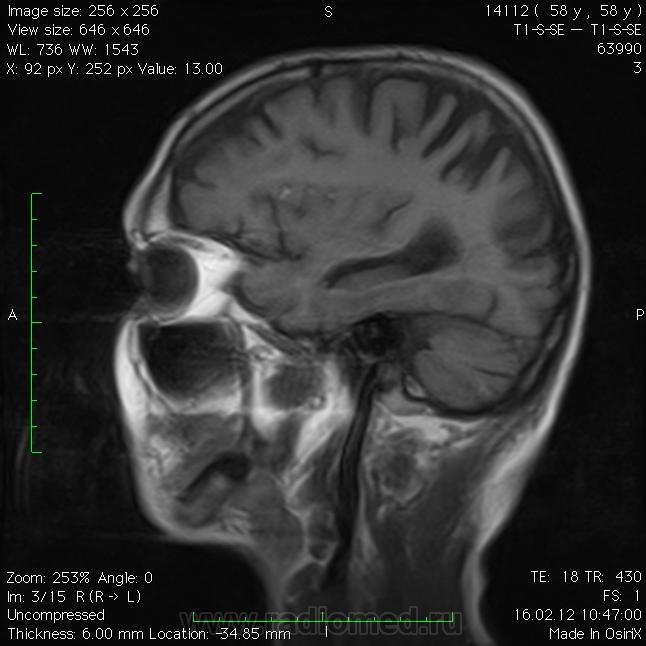

С одной стороны на кровь похоже в жлудочках, субарноидально и цистернах. Но с другой стороны вроде и плавает. Уровень есть по поверхности ликвора. Прорыв дермоидной кисты? Или дермоид - случайная находка при инфаркте? Мало информации.

http://www.radiomed.ru/cases/dermoid-golovnogo-mozga-0

http://www.radiomed.ru/cases/dermoid-golovnogo-mozga